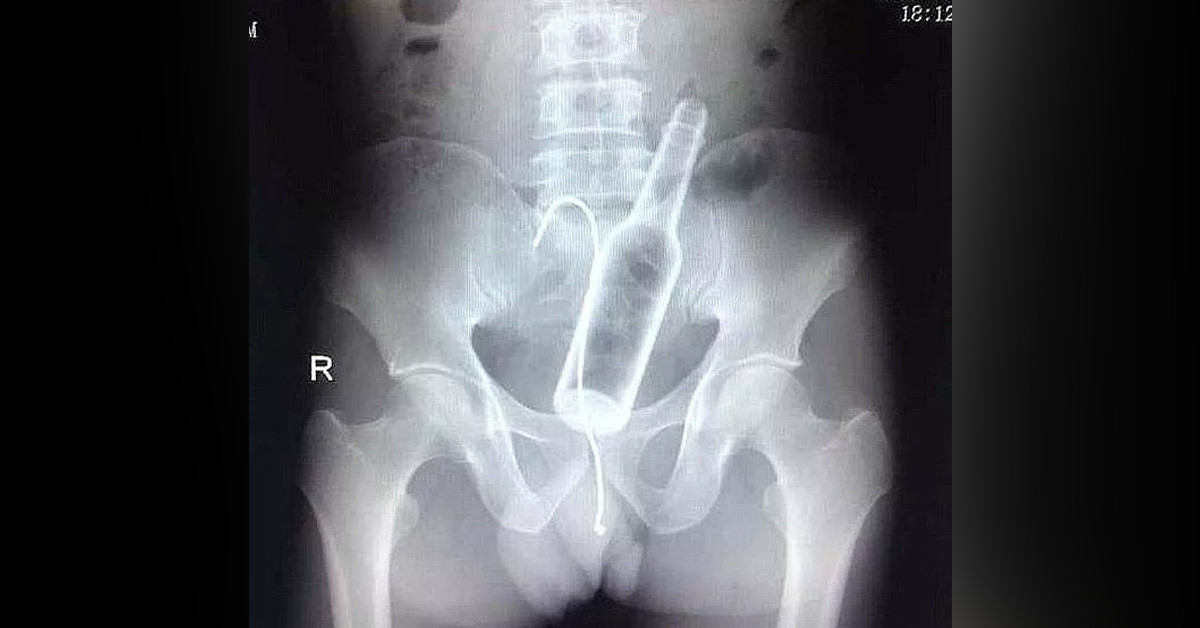

İranlı adamın bütün derdi, çektirdiği röntgen filmlerinin çıkmasıyla doktorlar tarafından anlaşıldı.

Doktorlar detaylı bir incelemenin sonucunda adamın makatında 12 santimetre boyutunda bir pet şişe buldu.